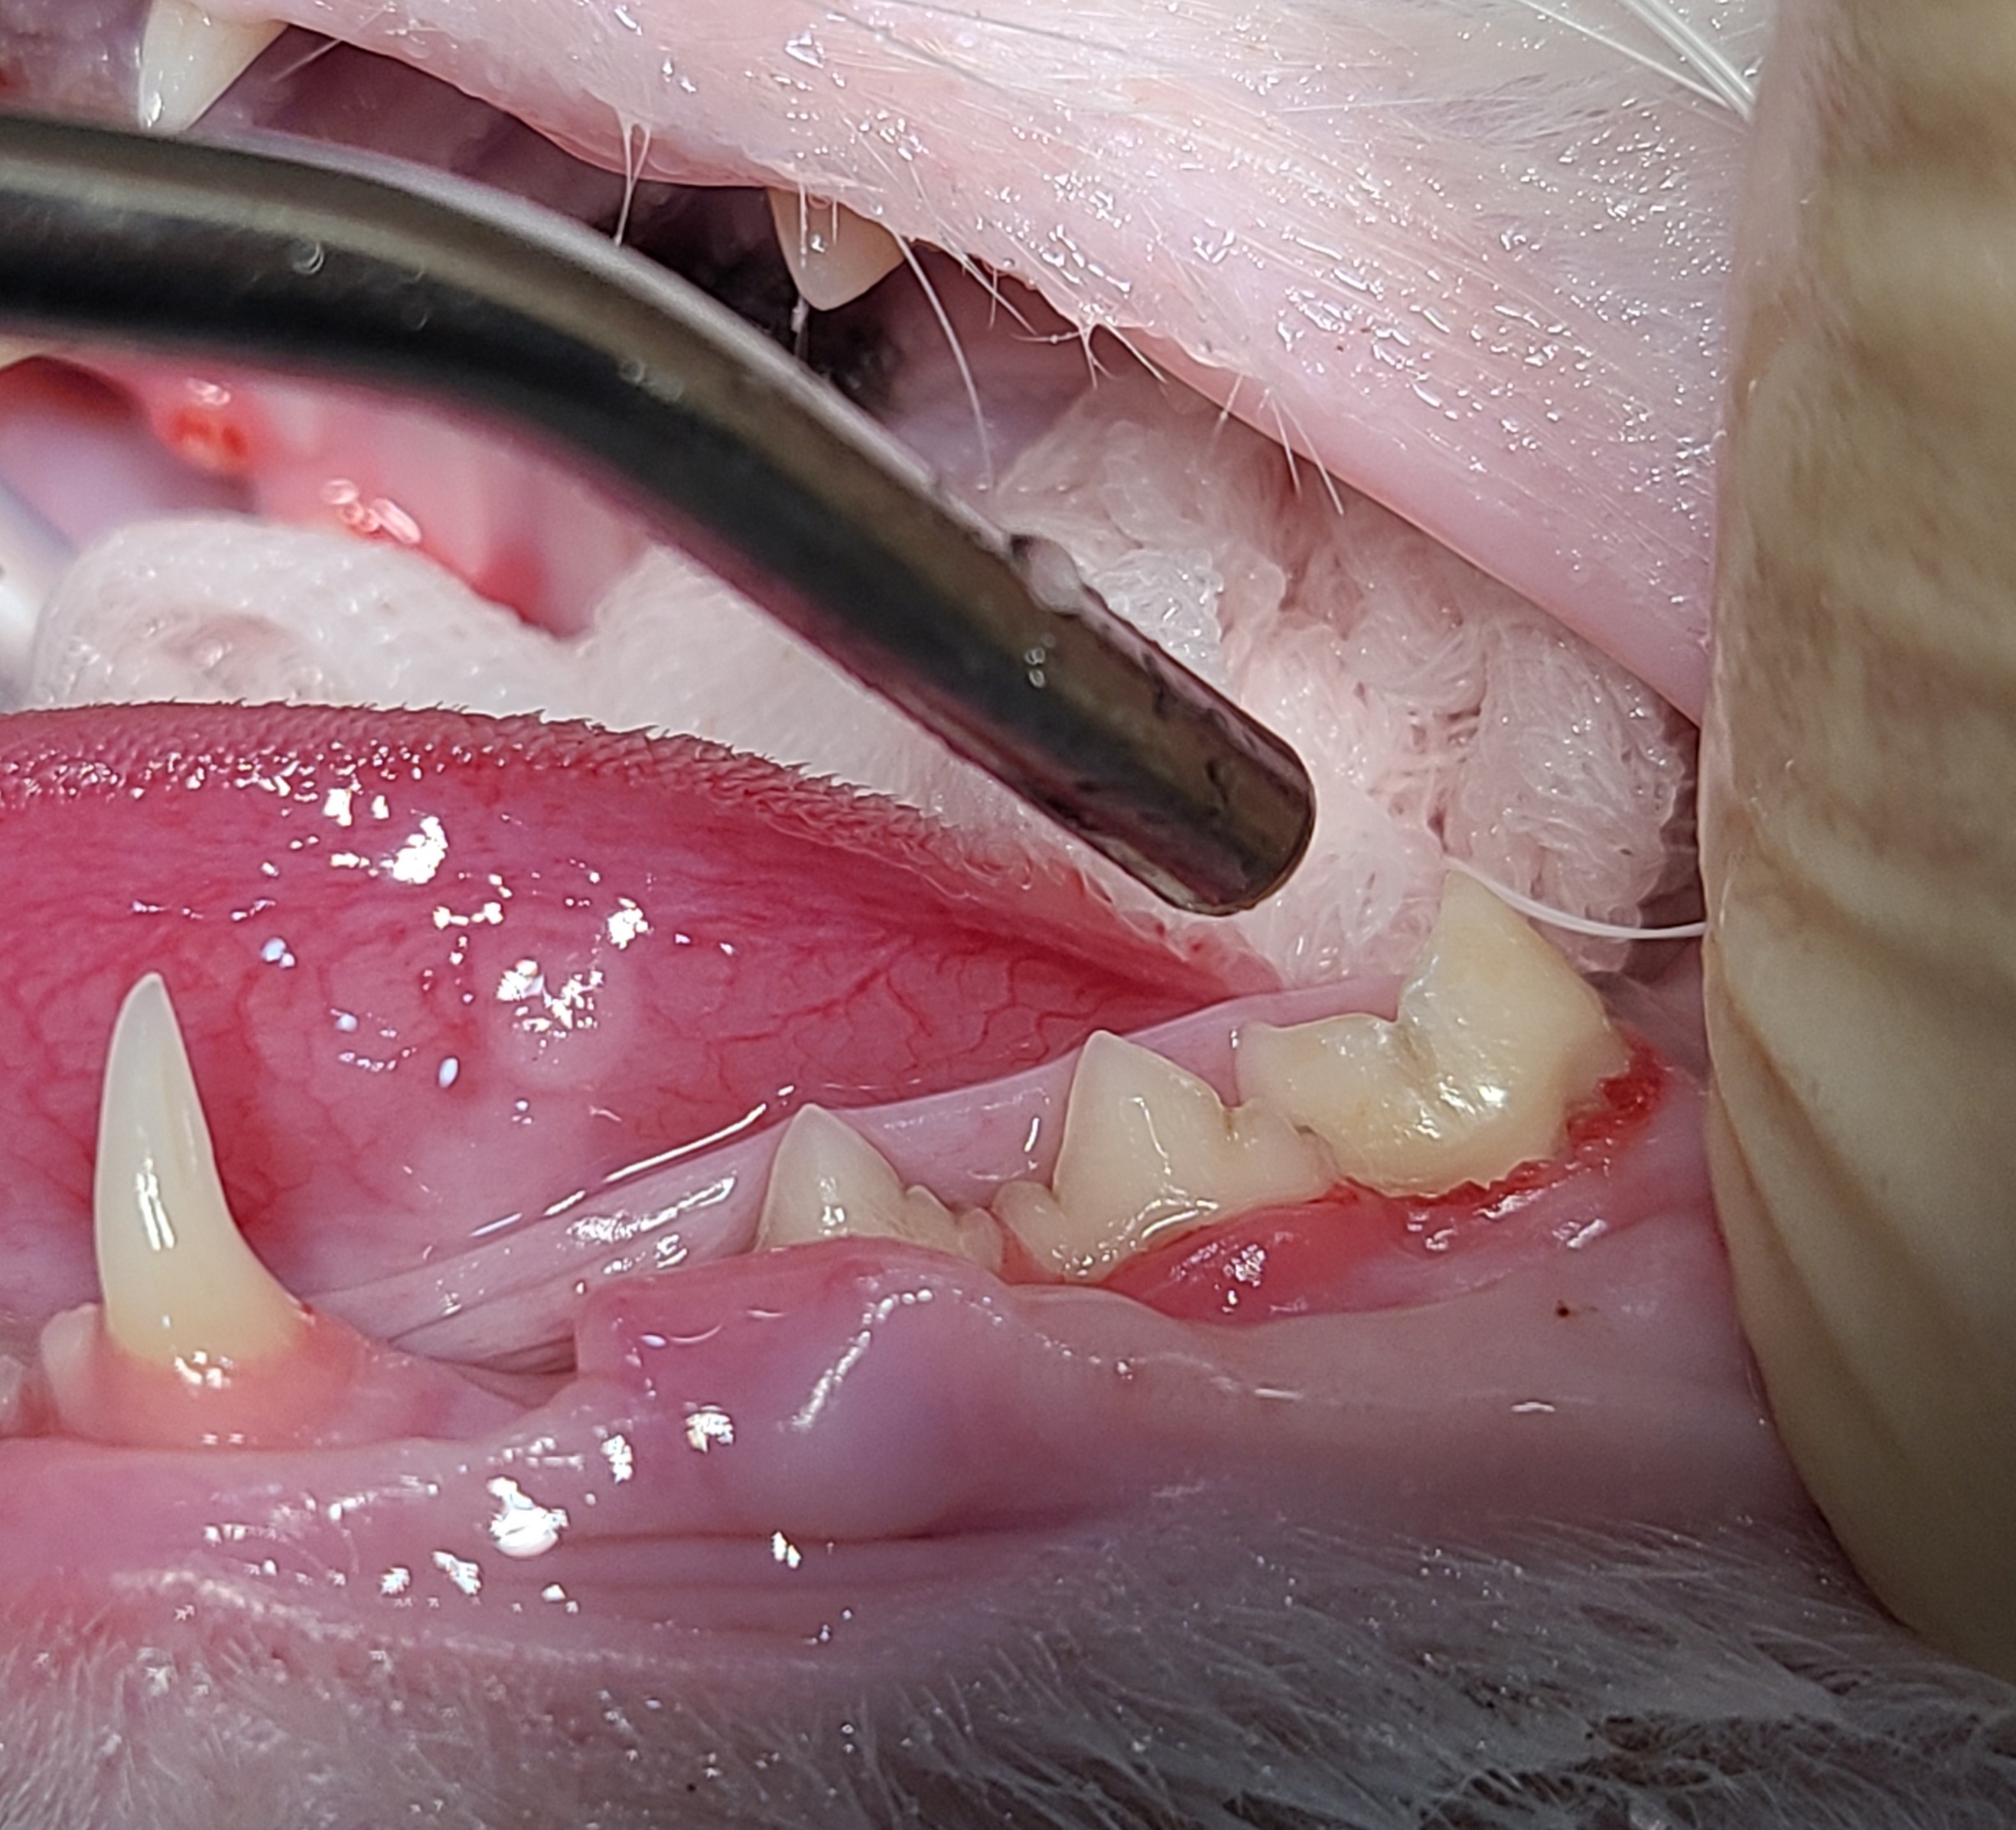

3시40분쯤 수술이제 들어간다고

연락이 왔고

한 시간 뒤쯤 잘 끝났다고 연락이 왔다.

6시까지 데리러 가기로 하고

바로 출발 했다.

선생님께서 친절하게 설명을 해주셨다.

스케일링을 하려고 봤는데

좋지 않은 이빨이 있어서

2개 뽑았다 하셨고

왼쪽 아래 어금니 3개는

우선은 살려뒀지만

2~3년 내에 발치를 해야할지도

모른다고 하셨다.

그리고 신장수치는

정상이었다!!